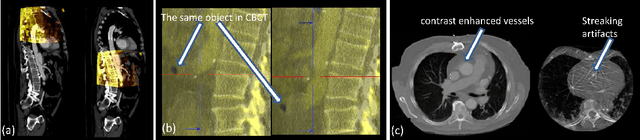

Abstract:3-D image registration, which involves aligning two or more images, is a critical step in a variety of medical applications from diagnosis to therapy. Image registration is commonly performed by optimizing an image matching metric as a cost function. However, this task is challenging due to the non-convex nature of the matching metric over the plausible registration parameter space and insufficient approaches for a robust optimization. As a result, current approaches are often customized to a specific problem and sensitive to image quality and artifacts. In this paper, we propose a completely different approach to image registration, inspired by how experts perform the task. We first cast the image registration problem as a "strategy learning" process, where the goal is to find the best sequence of motion actions (e.g. up, down, etc.) that yields image alignment. Within this approach, an artificial agent is learned, modeled using deep convolutional neural networks, with 3D raw image data as the input, and the next optimal action as the output. To cope with the dimensionality of the problem, we propose a greedy supervised approach for an end-to-end training, coupled with attention-driven hierarchical strategy. The resulting registration approach inherently encodes both a data-driven matching metric and an optimal registration strategy (policy). We demonstrate, on two 3-D/3-D medical image registration examples with drastically different nature of challenges, that the artificial agent outperforms several state-of-art registration methods by a large margin in terms of both accuracy and robustness.